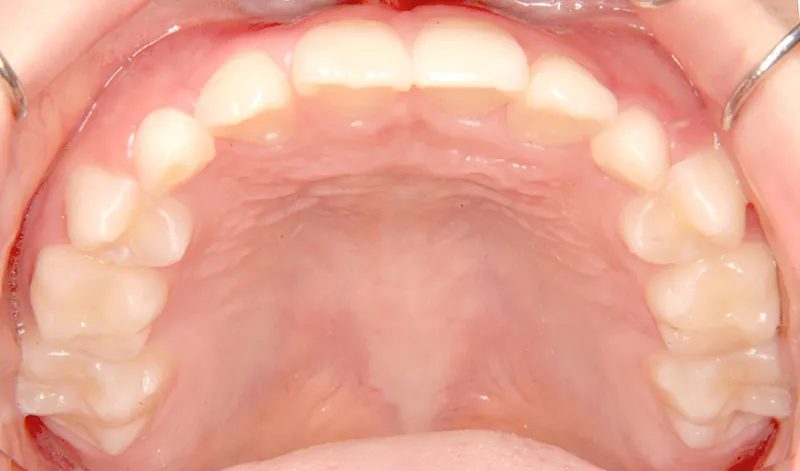

【子供の矯正(一期)】叢生・すきっ歯・永久歯が生える隙間がない・反対咬合・7歳男児【K.S様】

下の歯は永久歯の生えるスペースがないので、オリジナル矯正装置で受け口を治して、永久歯の生えるスペースを作りました。

治療回数19回、2年5ヶ月の治療期間で矯正治療を終了しました。

主訴が改善され、ご満足頂きました。

治療終了後